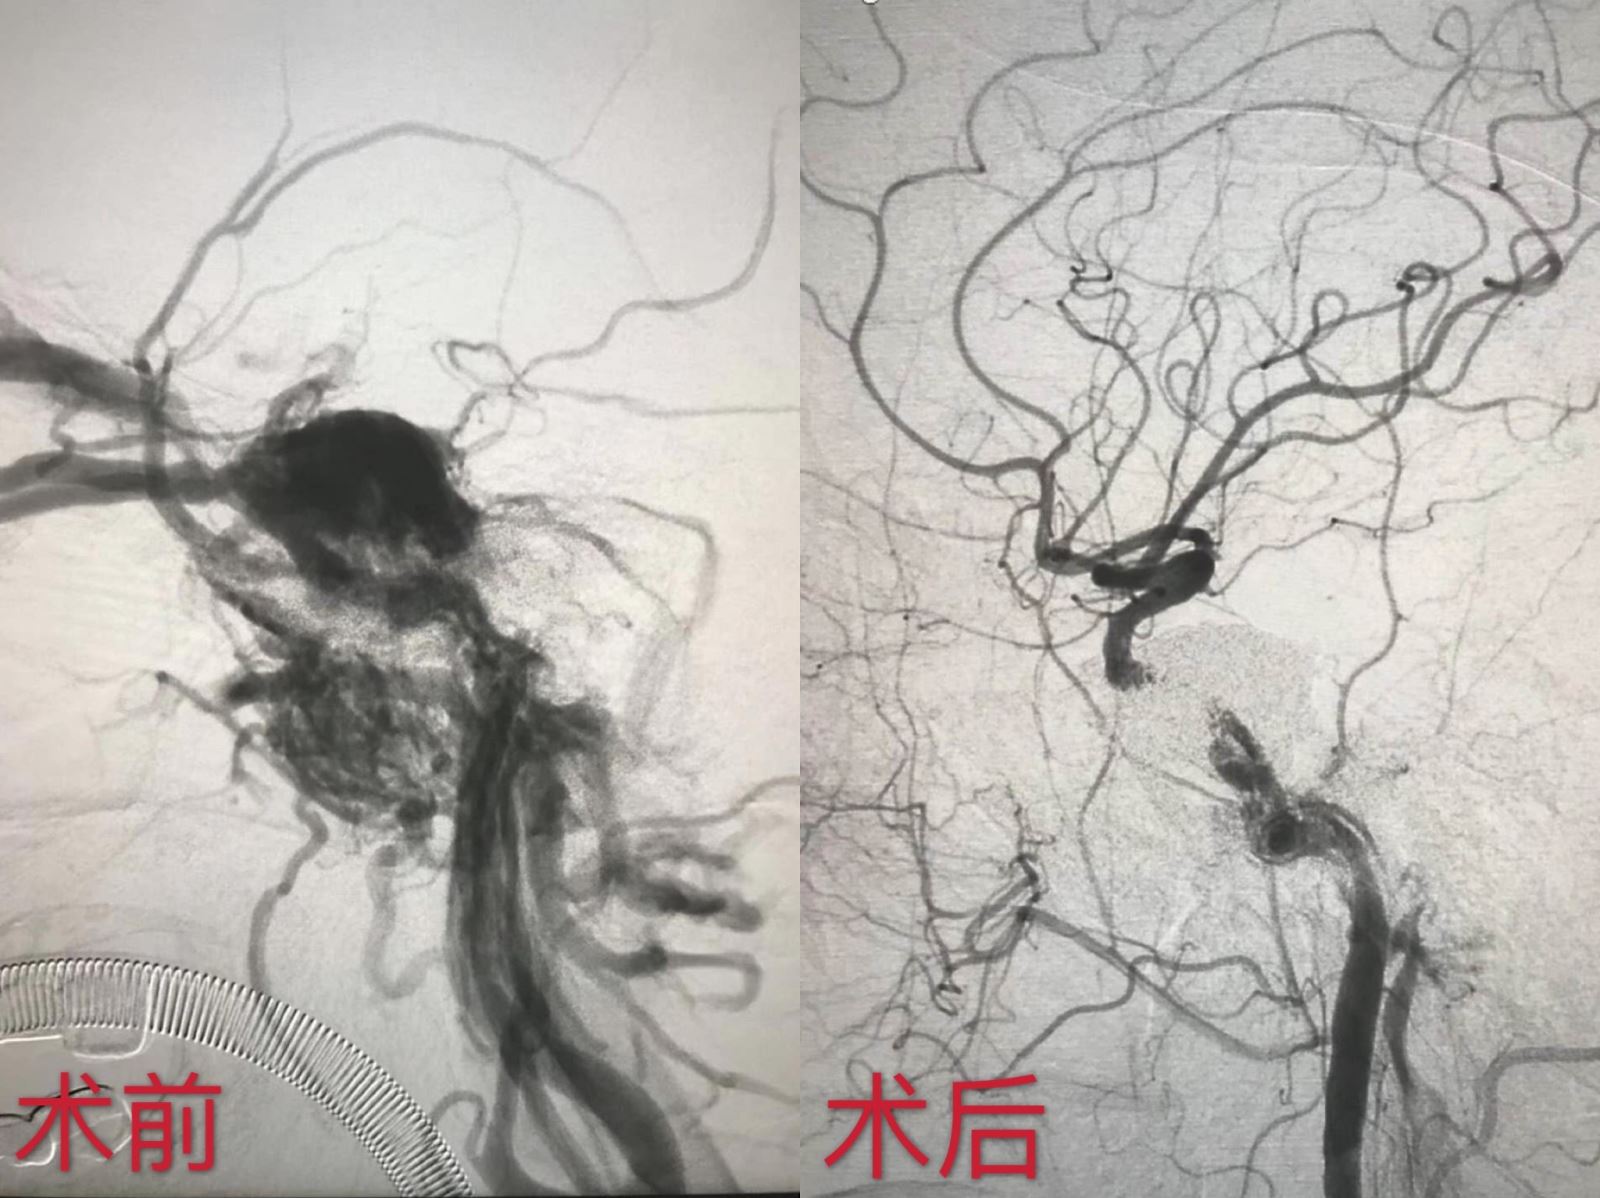

近日,我院东区神经外科完成通辽市首例颈动脉海绵窦瘘——弹簧圈辅助ONYX胶栓塞术,成功帮助患者解除病痛折磨,同时填补了我市神经外科技术空白。

据悉,颈动脉海绵窦瘘一般是由于外伤引起的负责大脑供血的颈动脉和负责静脉回流的海绵窦的直接沟通,是一种动静脉的“短路”,由于存在动脉与静脉之间的巨大血压差,这个瘘口一般无法自己闭合,也就是说这种疾病无法自愈。目前介入手术是治疗颈动脉海绵窦瘘的最好方法,传统外科手术治疗的难度和风险很大,但介入手术也存在一定的风险,主要是栓塞物的脱落导致颈动脉误栓,脑缺血甚至死亡。我院刘光宇主任带领科室治疗团队经过会诊讨论后,制定了周密、大胆的手术方案:先将弹簧圈填塞入瘘口,再用液态栓塞剂ONYX将瘘口残留的空间完全充填;填塞过程中应用顺应性球囊保护性阻断颈动脉,防止误栓造成脑梗死。这种治疗方法既能够保证患者的安全,又能够确保瘘口完全封堵。

经过与患者及家属的充分沟通,手术于8月17日实施。在北京宣武医院专家指导,张永哲医生、手麻科、介入科医生的默契配合下,经过4个小时的努力,手术圆满成功。术后,患者眼球明显回缩,充血及颅内杂音消失,视力恢复正常,平稳渡过了术后观察期,现恢复良好。